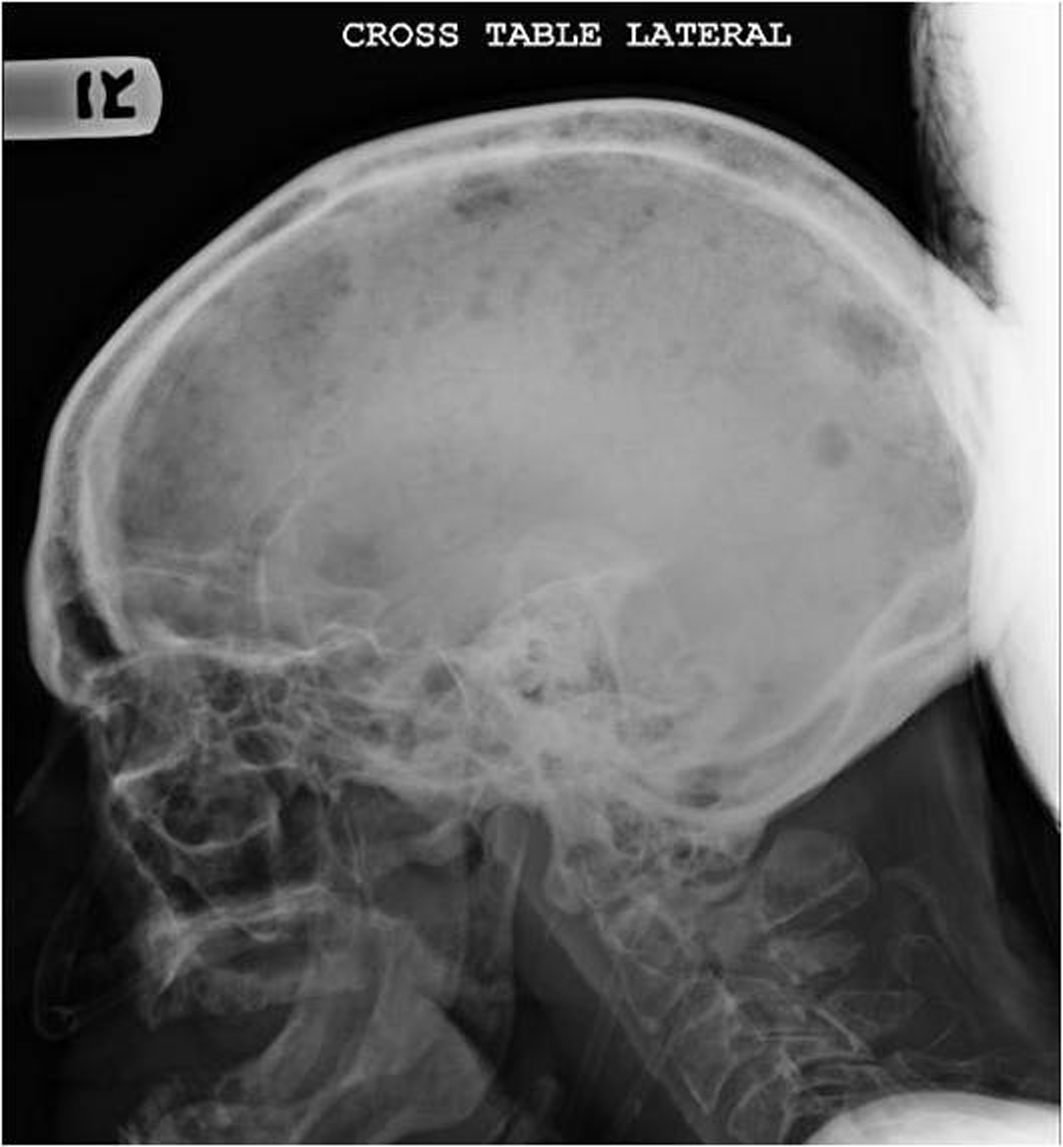

On admission patient was afebrile, hypotensive with blood pressure of 97/65, relatively bradycardic with heart rate of 67/minute and tachypneic with respiratory rate of 39/minute. General examination revealed cachectic old male with mild respiratory distress. Physical examination revealed bilateral cervical, axillary and inguinal hard, non matted lymphadenopathy; tachycardia and tachypnea. Physical examination was unremarkable otherwise including sensory and motor examinations. Laboratory investigations revealed leucocytosis with WBC count of 21,000/µL, normocytic normochromic anemia with hemoglobin of 7.6 g/dl. Blood chemistry showed sodium of 121 mmol/l, potassium 6.2 mmol/l, bicarbonate 5 mmol/l, BUN 95 mg/dl, serum creatinine 4.8 mg/dl, albumin of 1.8 g/dl, total protein of 8 g/dl, alkaline phosphates of 154 IU/l and corrected anion gap of 19.5. Blood gas analysis revealed mixed anion and non anion gap metabolic acidosis. Urine toxicology was negative including for alcohol. Urine analysis revealed proteinuria and hemoglobinuria. Other lab tests showed serum osmolarity of 320 mOsm/kg; urine osmolarity of 348 mOsm/kg and fractional excretion of sodium (FeNa) of 6.59. Chest X ray revealed multiple lytic areas in ribs and humerus with fracture of left 9th rib. X ray of the pelvis and x ray of the skull showed multiple lytic lesions (Fig. 1, Fig. 2). Patient was admitted with acute renal failure to rule out multiple myeloma and adrenal insufficiency.

![]() Click for large image | Figure 2. X ray of the skull showing multiple osteolytic lesions in the skull. |